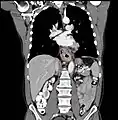

Additional testing is needed to assess how much the cancer has spread (see § Staging, below). Computed tomography (CT) of the chest, abdomen and pelvis can evaluate whether the cancer has spread to adjacent tissues or distant organs (especially liver and lymph nodes). The sensitivity of a CT scan is limited by its ability to detect masses (e.g. enlarged lymph nodes or involved organs) generally larger than 1 cm.[43][44] Positron emission tomography is also used to estimate the extent of the disease and is regarded as more precise than CT alone.[45] PET/MR as a novel modality has shown promising results in preoperative staging with fair feasibility and good correlation in comparison to PET/CT. It can enhance tissue differentiation with lowering the radiation dose to the patient.[46] Esophageal endoscopic ultrasound can provide staging information regarding the level of tumor invasion, and possible spread to regional lymph nodes.